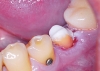

През лятото на 2010 г. - край морето, се запознах с д-р Ивелин Атанасов, той пък ме запозна с Константин Фиалковски и ми направиха проект на ослепителна усмивка - мечта. Цяла година д- р Иво работи тук в Бургас, в „Бо-дент” основно заради мен, съобразявайки се с моите безкрайни ангажименти и пътувания. Той, заедно с д-р Боги Димитров направиха всичко - лекуваха, рязаха, изравняваха по проекта, за да може накрая Fiadenta да ме короняса с уникалните си фасети.